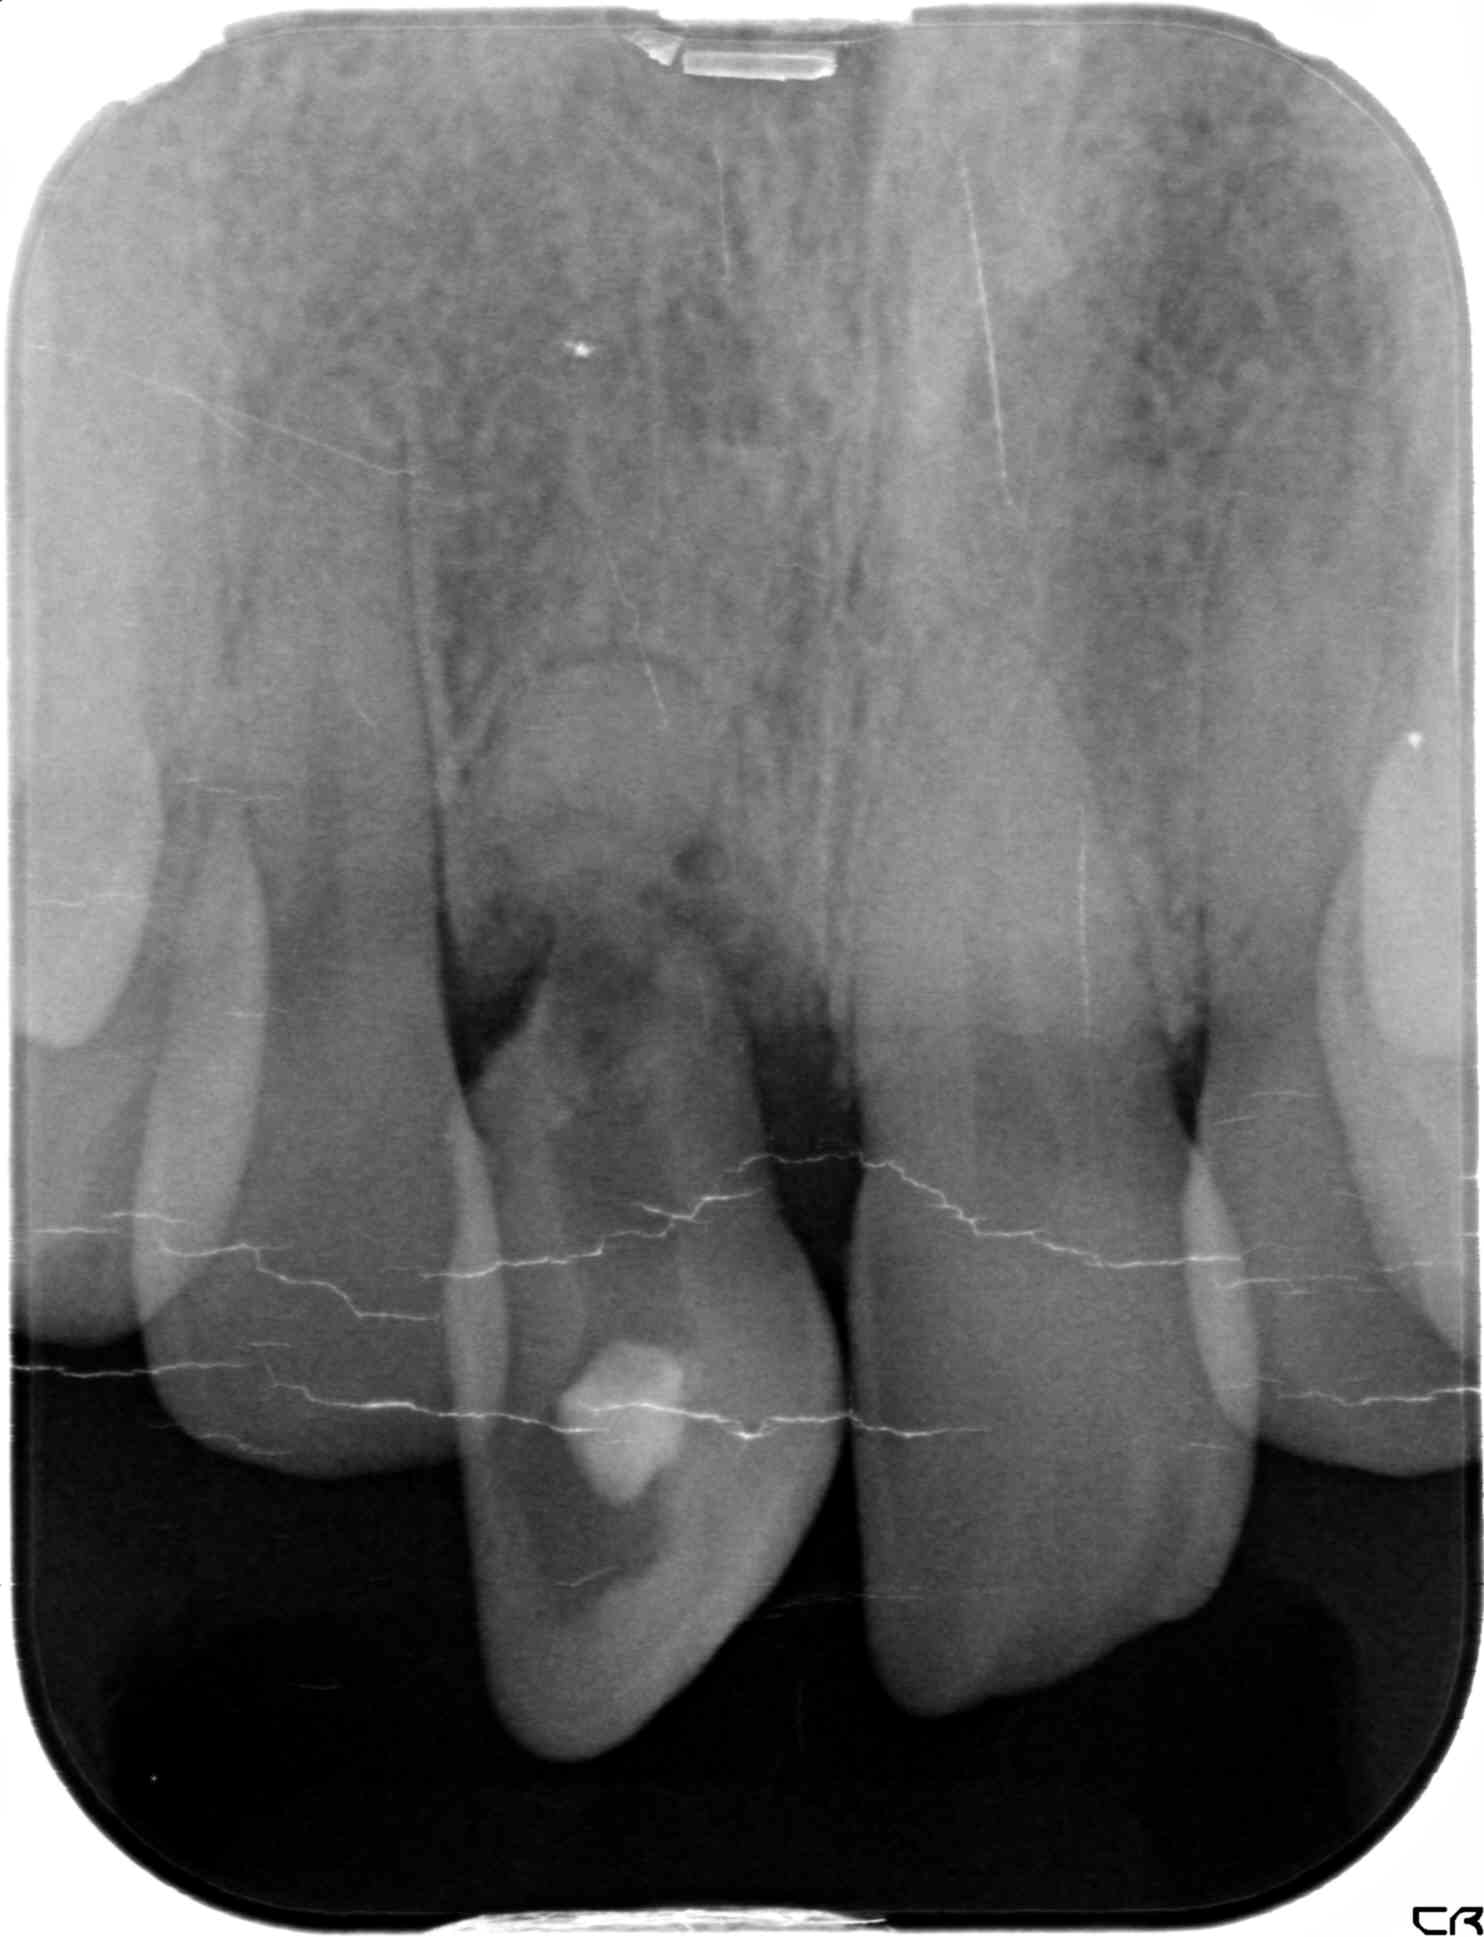

初診時、右上前歯がグラグラしており、抜歯およびインプラント治療をご希望されました。診査の結果、歯根が骨にほとんど埋まっておらず、保存は困難であったため、抜歯を行いました。

【レントゲン写真】